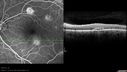

SPECTRALIS-SD-OCT SCAN: The OCT scan of the right eye shows the lesions to be predominately in the deep retina. There is clear loss of the photoreceptor integrity. The pigment epithelium looks normal in the area of the lesions, but above that the photoreceptor outer segments all the way up to the external limiting membrane lose their normal architecture and in some areas where the lesions are a little bit fresher, it looks like there is loss of the entire outer segment of the photoreceptors with only preservation of the nuclei. There is no evidence of any serous retinal detachment in either eye. The left eye similarly on the OCT scan shows over the lesion again a loss of photoreceptor integrity. There does appear to be a little bit of pigment epithelial irregularity over the dense lesion inferior to the fovea. The involvement goes all the way from the outer plexiform layer out to the retinal pigment epithelium. The edges of the lesions are sharp and no evidence of any spreading around them.